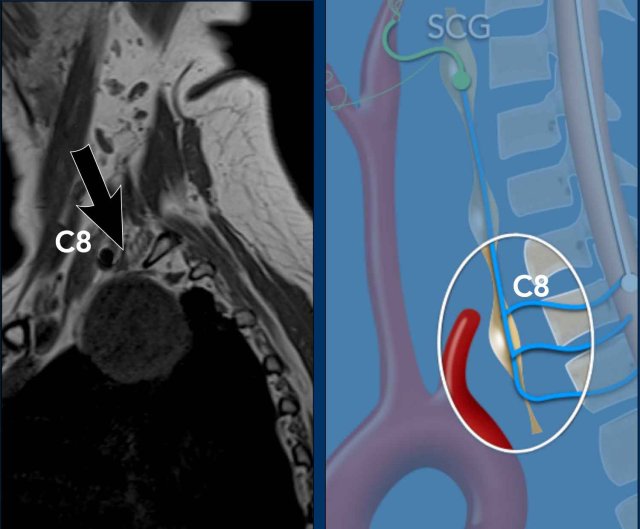

Case

These images are of a patient with a metastatic prostate cancer, who now presents with a paralysis of the hypoglossus on the right and a left-sided Horner.

Subsequently a CT of the neck and chest was performed, which showed a prevertebral mass at the level of C7-Th1.

This is the exact location of the inferior cervical ganglion.

A mass in this location explains the Horner on the left.